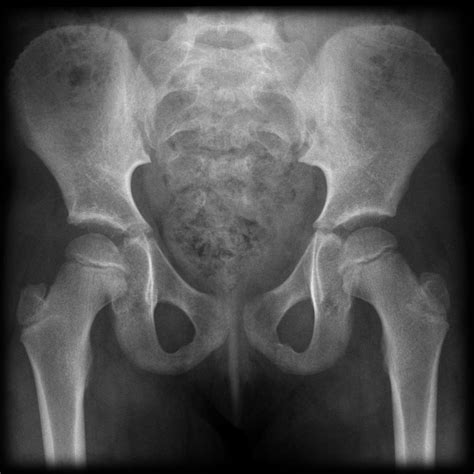

A Normal Hip X Ray is a radiographic image used to visualize the hip joint and surrounding structures. It helps in diagnosing a wide range of conditions, including fractures, dislocations, arthritis, and developmental abnormalities. The term โ€œnormalโ€ refers to the expected appearance of the hip joint in the absence of any pathological conditions.

Interpreting a Normal Hip X Ray requires a trained eye. Radiologists look for specific features to determine the health of the hip joint. Key elements include:

• Bone Density: The density and structure of the bones should appear uniform and without any fractures or lesions.

• Joint Space: The space between the femoral head and the acetabulum should be consistent and without narrowing, which could indicate arthritis.

• Alignment: The femoral head should be properly seated within the acetabulum, and the neck of the femur should align correctly with the shaft.

• Soft Tissues: The surrounding soft tissues should appear normal, without any swelling or abnormalities.

Understanding the results of a Normal Hip X Ray involves interpreting the images for any abnormalities. Here is a breakdown of what to look for:

Feature Normal Appearance Abnormal Appearance

Bone Density Uniform and consistent Fractures, lesions, or areas of increased or decreased density

Joint Space Consistent and even Narrowing or irregularities

Alignment Proper seating of the femoral head Misalignment or dislocation

Soft Tissues Normal appearance Swelling, masses, or other abnormalities